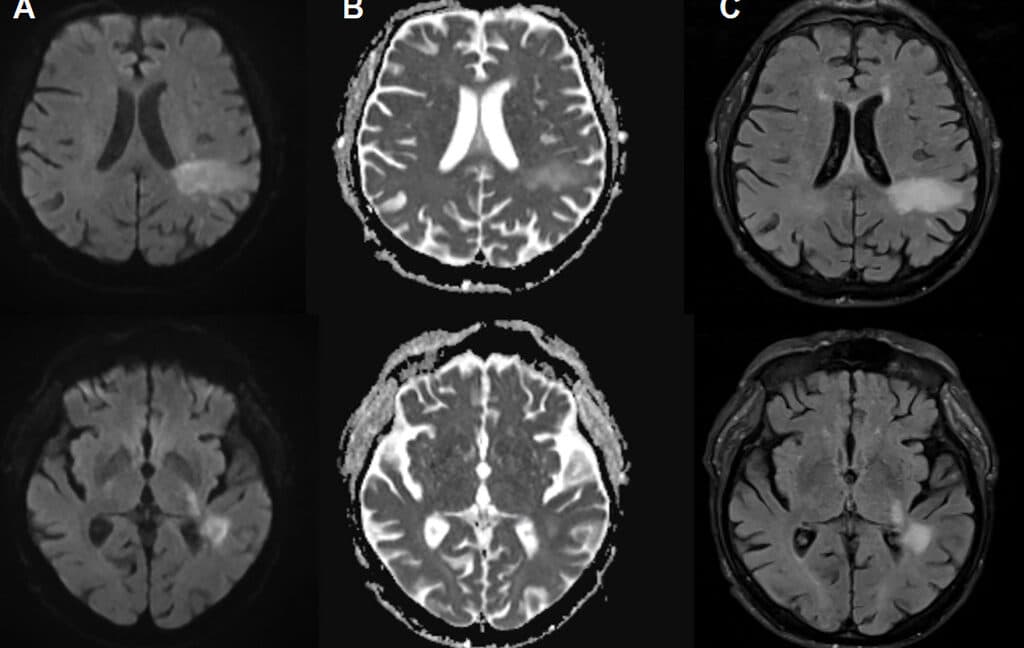

Fatal brain infection was thought to be from profound immune suppression. Not anymore.